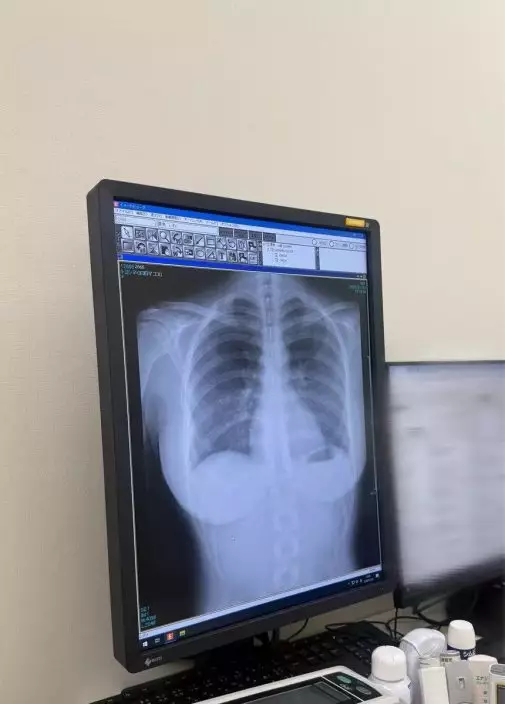

綜合日媒報導,日本一名22歲新生代寫真偶像豐島心櫻除拍攝寫真集外,也曾參演改編自《戀上換裝娃娃》的真人版日劇。憑藉甜美外貌及亮眼身材,深受粉絲喜愛。1月23日,豐島心櫻於社交平台X上載一張胸部X光影像向粉絲交代體檢結果,並留言表示「肺很乾淨」。

女星曬黑白X光照報平安,胸部線條被清晰展示震撼全網。X平台圖片

胸部輪廓清晰呈現 網民留言熱議

然而,該張黑白X光片卻意外將豐島心櫻的胸部輪廓清晰呈現,帖文隨即在網上迅速瘋傳,短短兩日內已累積超過4000萬次瀏覽,引起網民熱烈討論,不少人更直言「第一次看到這麼驚人的X光片、太刺激了」、「肺在哪?我只看到……」、「寫真偶像的X光片太刺激了」、「這是我第一次看到這麼驚人的X光片」。

網民提醒或有脊椎側彎 籲注意姿勢與健康

也有部分細心網民指出,從影像中似乎可見豐島心櫻有輕微脊椎側彎的情況,並留言提醒她平日要多加註意坐姿及身體狀況。